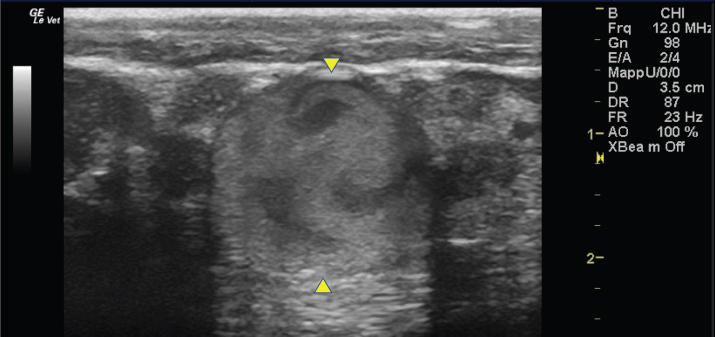

The left jugular vein appeared as an anechoic tubular structure which collapsed under the probe pressure, the color Doppler examination revealed normal blood flow within the vessel (Fig. 3). Bi-dimensional ultrasonography of the right jugular vein showed a heterogeneous, non-cavitating, hypoechoic structure occluding a narrowed right jugular vein for about 30 cm of length localized in the proximal and mid-portion of the neck compatible with a thrombus (Fig. 4). The color Doppler examination showed blood flow through the lateral portions of the thrombus in the cranial and mid-portions of the right jugular vein (Fig. 5). Cranially to the thrombus, a marked distension of the maxillary and linguofacial veins was evident, with a turbulent and echogenic flow; the latter was compatible with blood stasis near the thrombus (Fig. 6). Caudally to the thrombus, the right jugular vein presented reduced diameter, thickened walls, and normal blood flow (Fig. 7). The cranial part of the thrombus originated from a heterogeneous scare tissue, localized at the level of the right mandibular angle (Fig. 8). After injection of the first saline contrast bolus in a right facial vein, no microbubbles appeared in the right jugular vein, caudally to the thrombus, proving the presence of a complete right jugular vein occlusion. On the contrary, after injection of the second bolus, microbubbles were visualized in the left jugular vein as small, intense, echo signals within the vein lumen, demonstrating the presence of collateral circulation that drained the blood from the right facial veins to the left jugular vein (Fig. 9). Venography results confirmed the complete occlusion of the right jugular vein and the presence of submandibular venous collaterals that connected the right facial veins with the left jugular vein (Figs. 10 and 11). Based on the previous results, the diagnosis of JVT with complete occlusion of the vessel lumen was confirmed. The horse’s owner refused any proposed medical or surgical therapy.

Fig. 6. Bi-dimensional ultrasonographic image of the dilated right maxillary vein (between arrowheads). Note the turbulent and echogenic flow compatible with blood stasis near the thrombus.